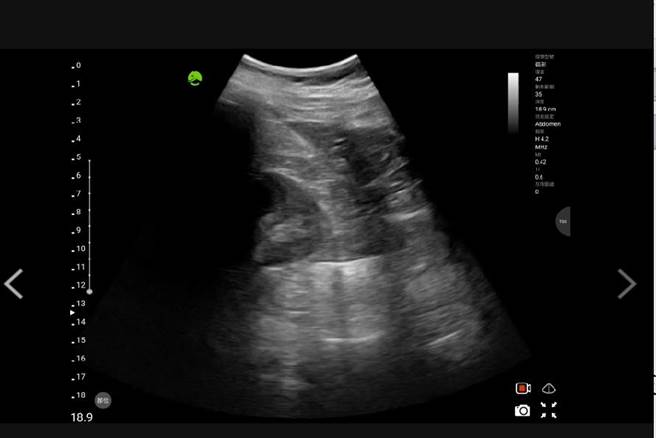

云林县消防局救护人员为提早确认伤患是否有出血现象,首次使用院前超音波扫描,并上传医师群组判读。(云林县消防局提供)

翻覆的白色厢型车上包含杨姓驾驶共4人搭乘,杨男获救时主述「左腹疼痛」,高级救护技术员(EMPT)立即使用超音波扫瞄上传医师群组,提早让医生确定是否有内出血,所幸受伤不重,这也是云林县消防局首次使用超音波抢救的案件。